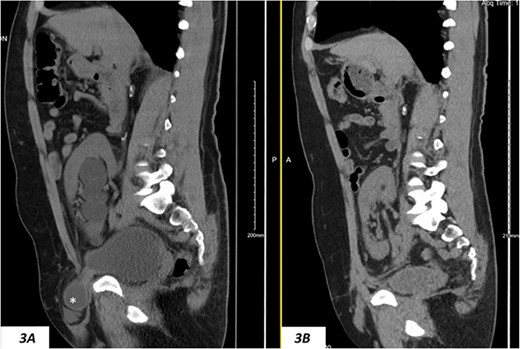

(A) Hydronephrosis on preoperative sagittal CT scan showing the reported dilated part of the distal ureter (*), which was correctly identified intraoperatively as a sliding dome of the bladder; note the relationship to the pubic bone; (B) significant improvement of hydronephrosis on the 10-month postoperative image.